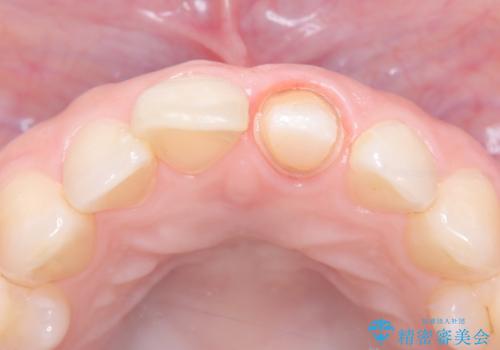

- 以前の根管治療後に生じた左上1番の前歯の変色を気にされて来院されました。患者様のご希望を伺い、オールセラミッククラウンによる審美修復を提案。既根管治療歯であるため、土台の状態や周囲の歯の色調を詳細に分析し、患者様の顔貌に調和した自然で美しい口元を実現するための治療計画を立てました。

治療では、変色した歯を形成した後、精密なシリコン印象材で型取りを行いました。この型取りから、患者様の歯の色や形、透明感を忠実に再現したオーダーメイドのオールセラミッククラウンを作製。金属を一切使わないため、アレルギーの心配がなく、歯ぐきの変色も防ぎます。技工士と連携し、天然歯と見分けがつかないほどの自然な仕上がりを追求。機能性と審美性を兼ね備えた、理想的な前歯を取り戻していただけました。